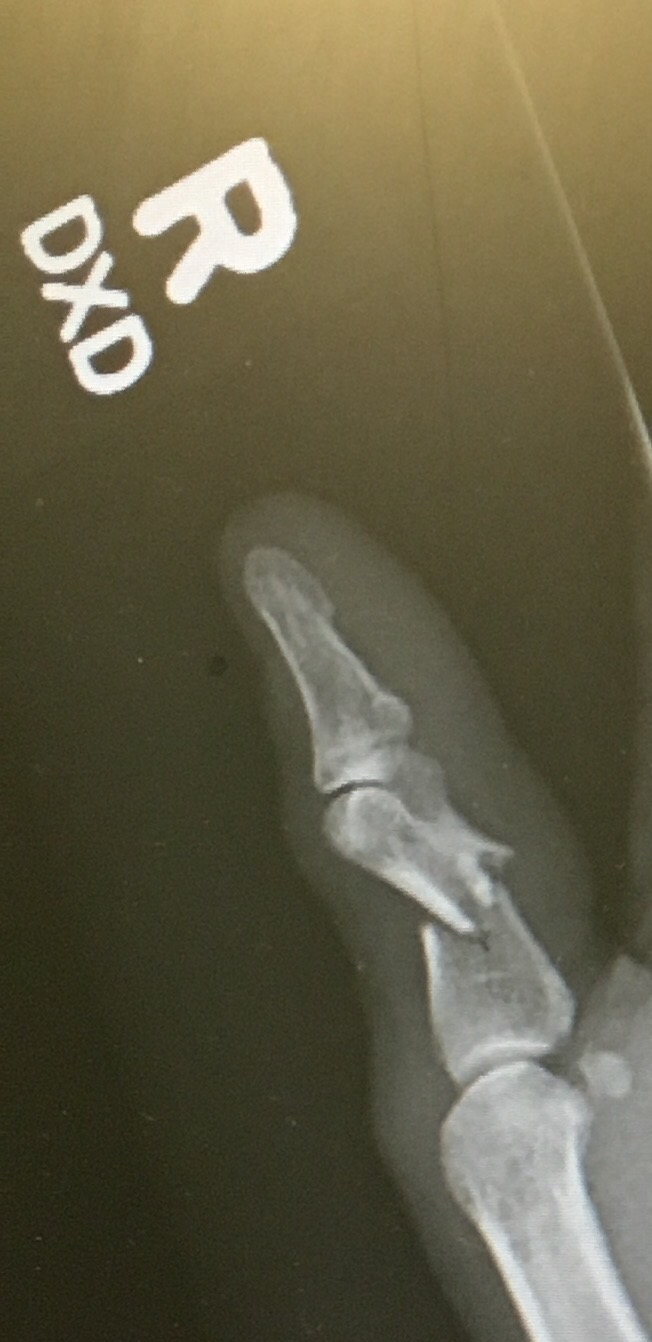

This was the initial fracture.